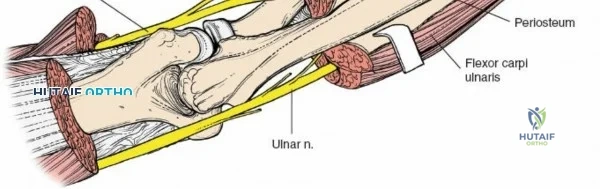

Deep Surgical Dissection: Exposing the Proximal Third

Exposing the proximal third of the radius requires extreme vigilance due to the proximity of the posterior interosseous nerve. The key anatomical landmark here is the insertion of the biceps tendon. Follow the biceps tendon distally to its insertion on the bicipital tuberosity of the radius. A small bursa lies just lateral to the tendon; incise this bursa to gain initial access to the proximal radial shaft. Because the radial artery lies superficial and medial to the tendon at this level, all deep dissection must remain strictly lateral to the biceps tendon.

The proximal radius is draped by the supinator muscle. The PIN passes directly through the belly of the supinator. To protect the nerve, the forearm must be fully supinated. Supination dynamically rotates the radius, carrying the insertion of the supinator anteriorly and simultaneously displacing the PIN laterally and posteriorly, safely away from the surgical field.

With the forearm fully supinated, identify the broad insertion of the supinator on the anterior aspect of the radius. Incise the supinator directly along the line of its insertion onto the bone. It is critical to detach the muscle by dividing its insertion sharply at the bone, rather than splitting the muscle belly, which would risk cutting the PIN.

Proceed with strict subperiosteal dissection, elevating the supinator laterally off the bone. This is one of the rare instances in orthopedic surgery where the safety gained by staying in a subperiosteal plane completely outweighs the theoretical vascular damage to the bone caused by periosteal stripping. The elevated supinator muscle belly now acts as a protective cushion for the PIN.

Retractor Placement and Fixation Technique

Once the proximal radius is exposed, great care must be taken with retractor placement. Never place Hohmann or levering retractors blindly around the posterior surface of the radial neck. Because the PIN may touch the bone posteriorly in up to 25% of patients, a posteriorly placed retractor can easily crush the nerve against the radial cortex. Instead, use gentle right-angle retractors or place retractors only on the anterior and lateral aspects of the bone, utilizing the elevated supinator as a shield.